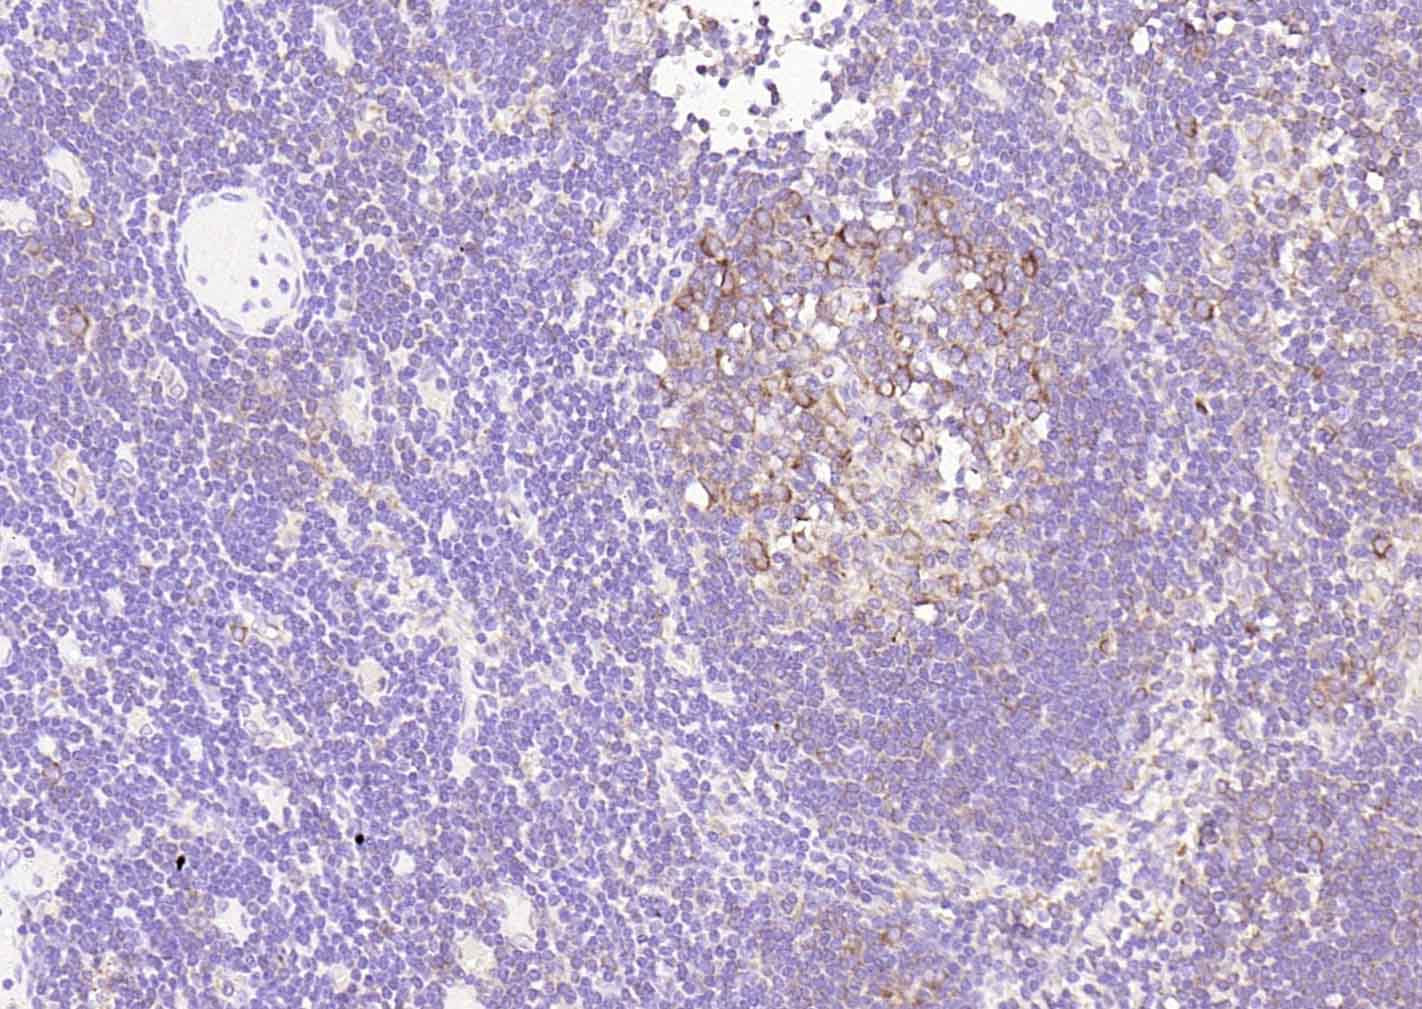

Paraformaldehyde-fixed, paraffin embedded (human lymphoid); Antigen retrieval by boiling in E sodium citrate buffer (pH6.0) for 15min; Block endogenous peroxidase by 3% hydrogen peroxide for 20 minutes; Blocking buffer (normal goat serum) at 37°C for 30min; Incubation with (CD25) Monoclonal Antibody, Unconjugated (bsm-60613R) at 1:50 overnight at 4°C, followed by operating according to SP Kit(Rabbit) (sp-0023) instructionsand DAB staining.

Paraformaldehyde-fixed, paraffin embedded (human tonsil); Antigen retrieval by boiling in E sodium citrate buffer (pH6.0) for 15min; Block endogenous peroxidase by 3% hydrogen peroxide for 20 minutes; Blocking buffer (normal goat serum) at 37°C for 30min; Incubation with (CD25) Monoclonal Antibody, Unconjugated (bsm-60613R) at 1:50 overnight at 4°C, followed by operating according to SP Kit(Rabbit) (sp-0023) instructionsand DAB staining.